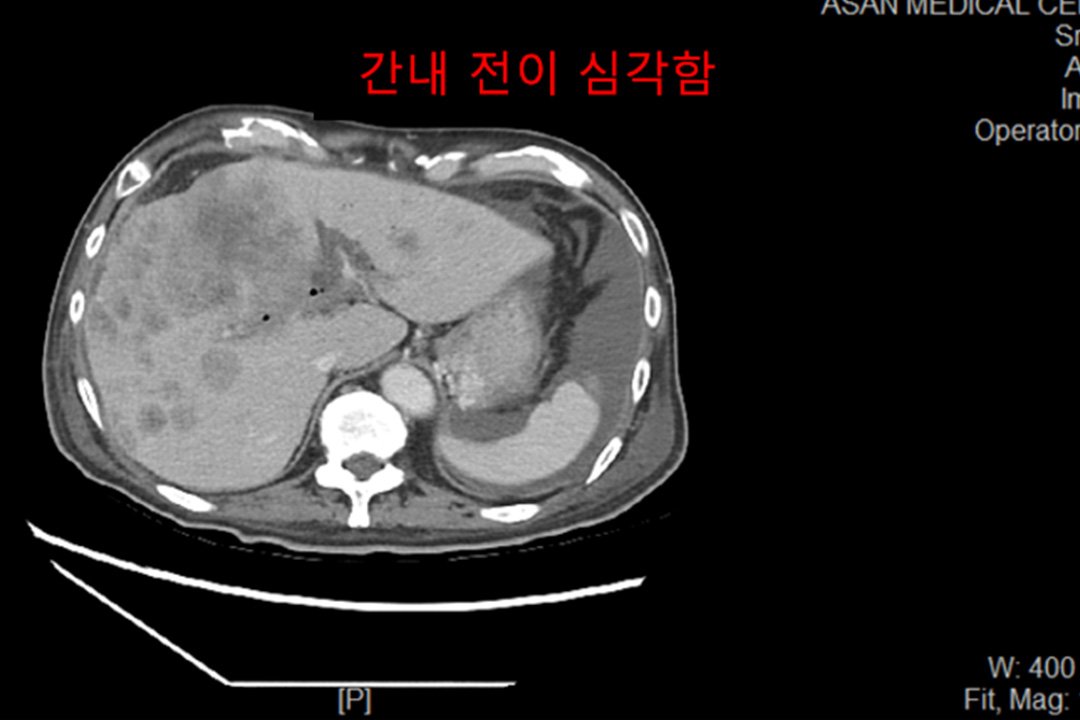

Case of treatment

아미랑에서 치료하신 분들의 소중한 치료사례를 담았습니다.